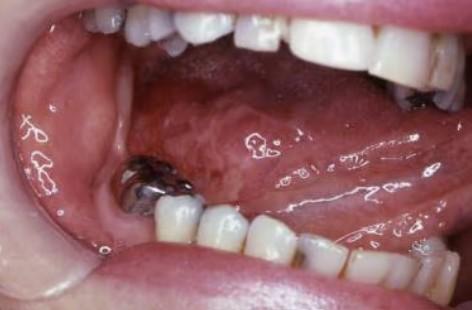

Squamous cell carcinoma of the tongue

Benign or Cancerous?

Benign lesions are an abnormal growth of cells which do not spread to other regions of the body. Some may grow to a size where they cause damage to local structures. Benign lesions may require surgery. Â Some benign lesions reoccur and need monitoring over several years.

Cancerous lesions are an abnormal growth of cells which invade nearby tissues. These cancers can move into your blood stream and lymph nodes, and can spread to other parts of the body. Cancerous lesions usually require urgent surgical attention. Other cancer specialists will also be involved in your care.